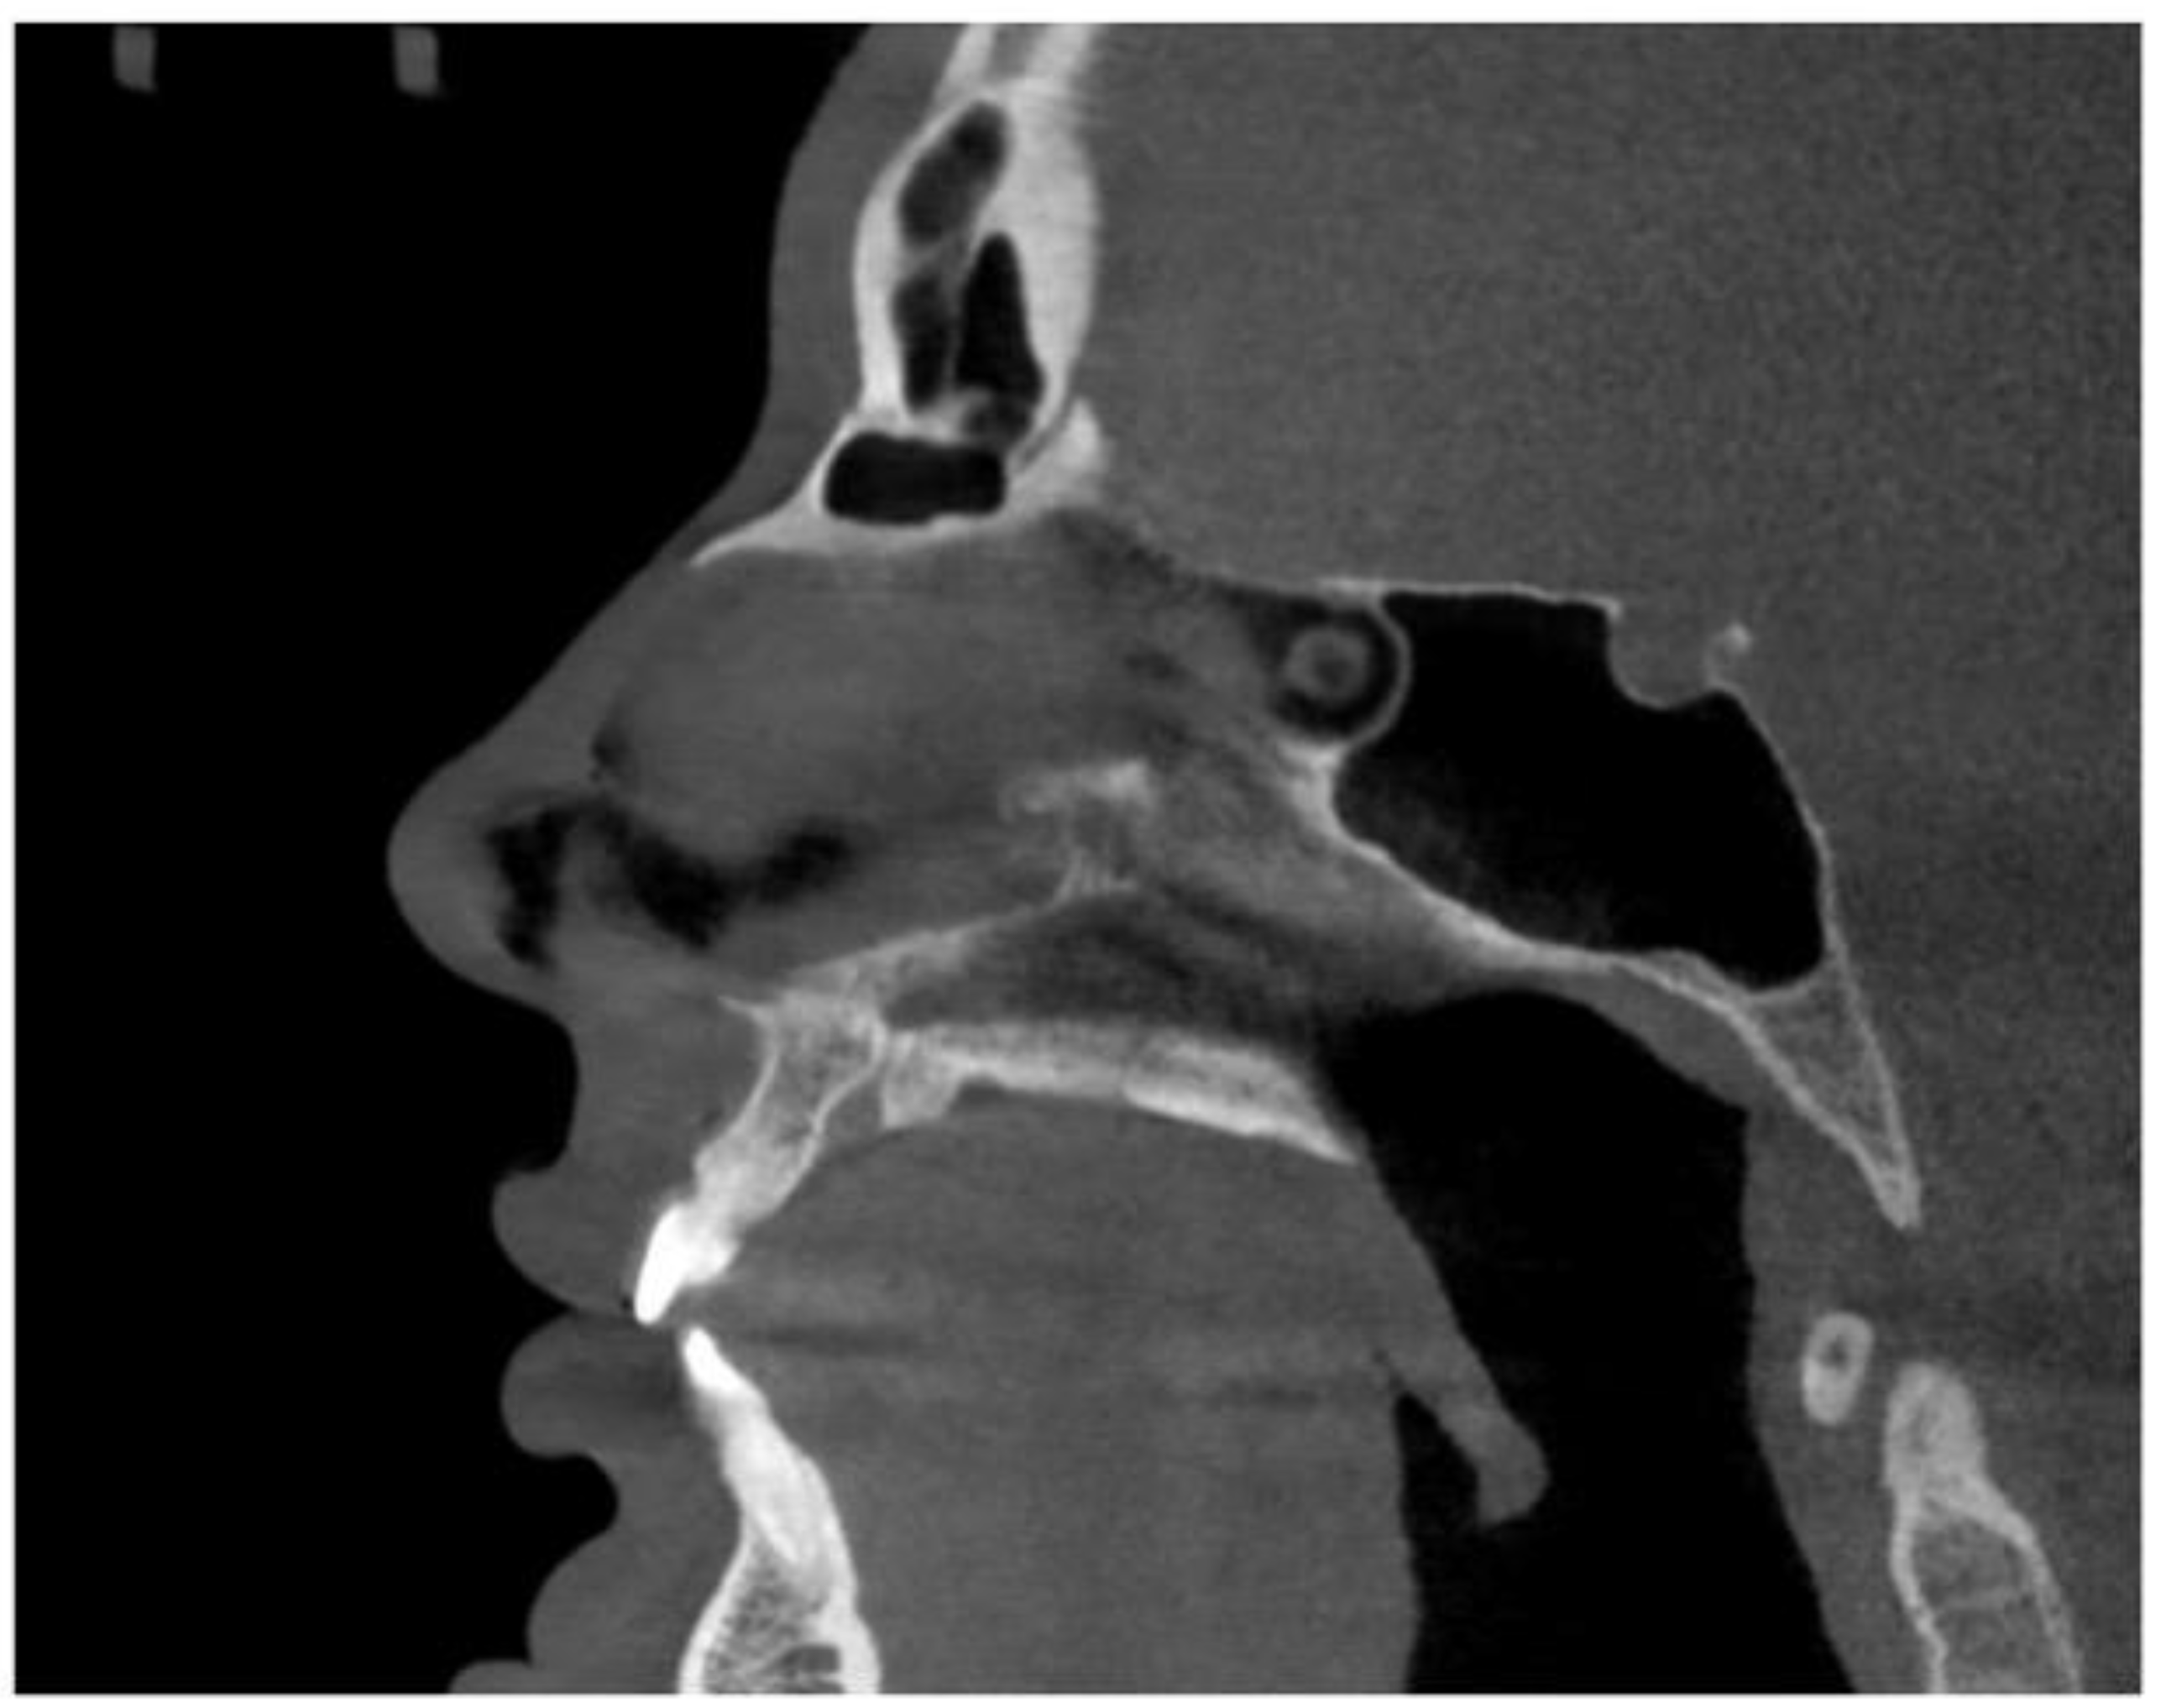

2.4. Case A: Blind Midpalatal Piezocorticotomy with MARPE Expansion